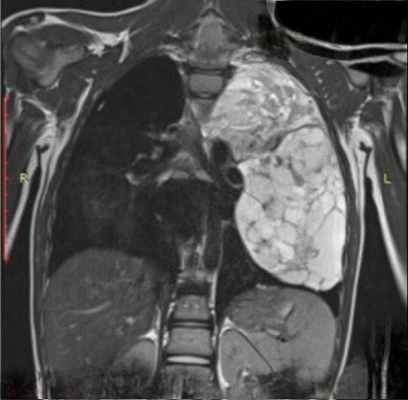

В тех случаях, когда эти опухоли (что, к счастью, бывает редко) озлокачествляются и приобретают крупные размеры, тогда судить о природе, источнике чрезвычайно сложно. Это злокачественная нейрогенная опухоль, которая привела к оттеснению средостения в противоположную сторону – в сторону правого легкого с накоплением жидкости в правой половине плевральной полости.

Огромных размеров патологическое образование, оттесняющее аорту впереди в сторону сердца, занимающее практически всю левую половину грудной полости, оттесняющее селезенку, почку и диафрагму вниз. Это злокачественная нейрогенная опухоль. Но сказать о том, что эта опухоль исходит из нервных образований, при томографическом исследовании очень сложно и не всегда возможно.